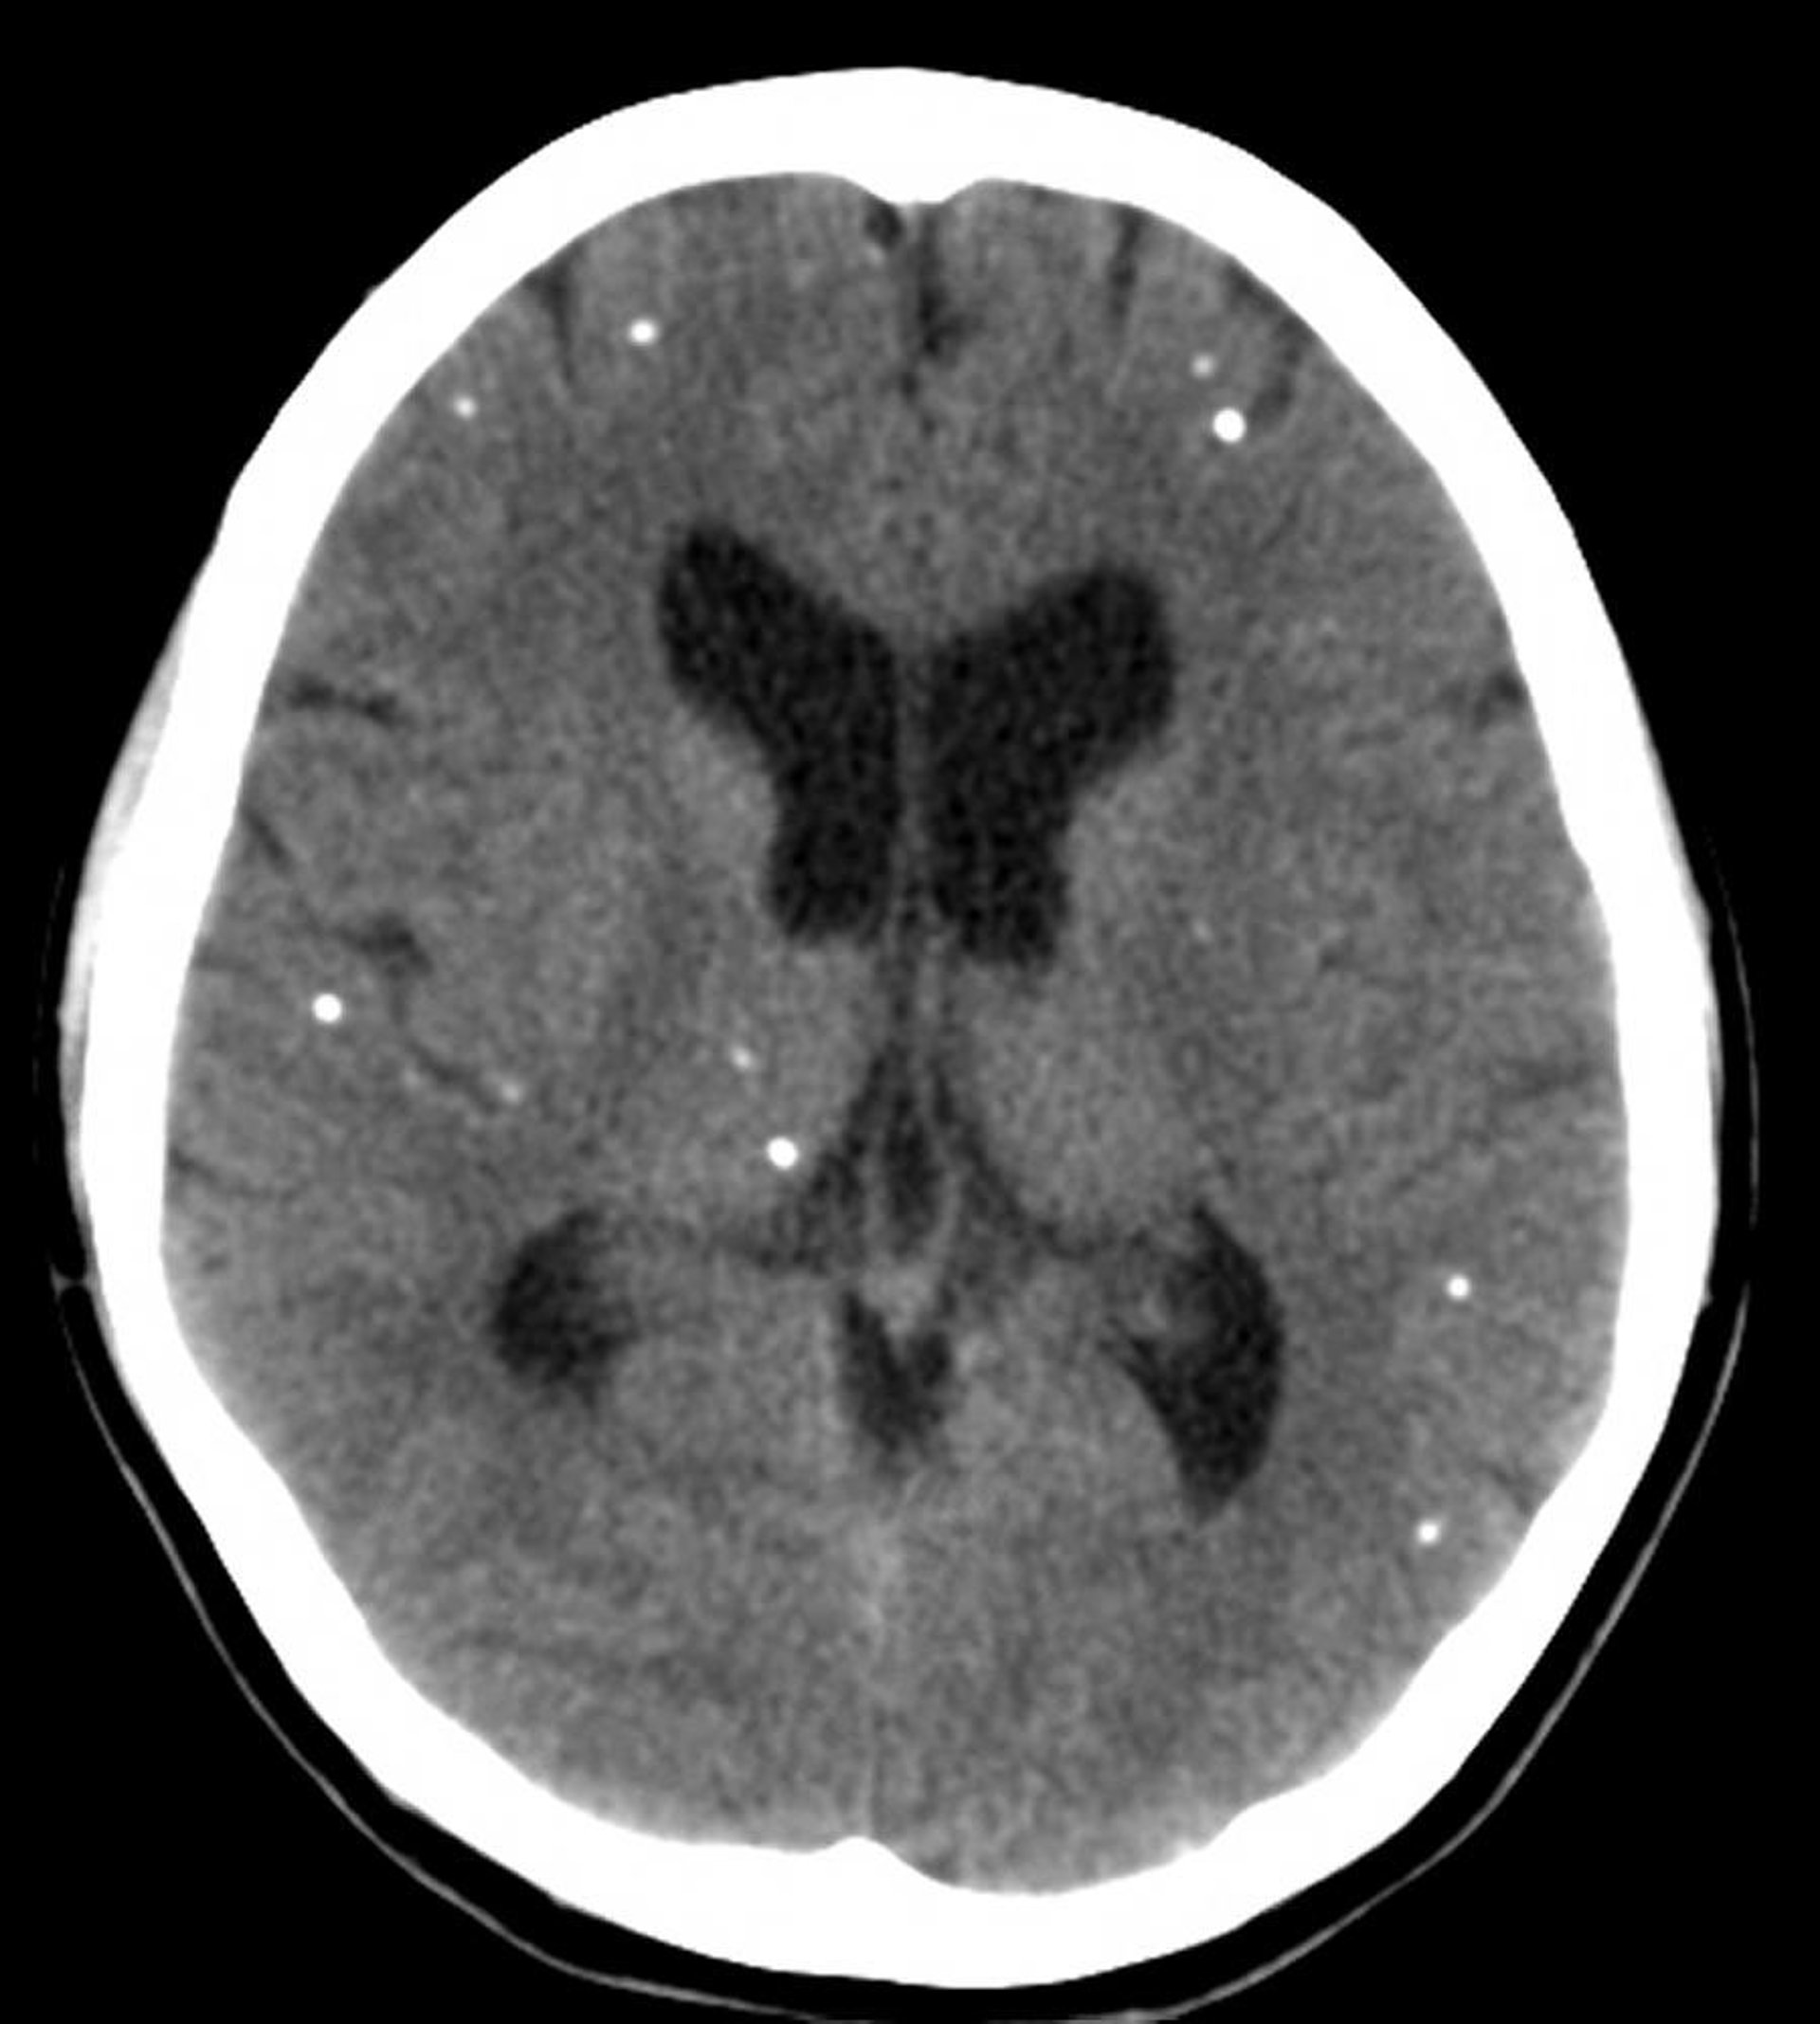

Questa scansione TC mostra aree multifocali di calcificazione che rappresentano cisti calcificate in un paziente con neurocisticercosi.